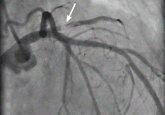

ArticleA rare complication of infective endocarditisAuthor:Megan J. DeKam, DOPublish date: May 1, 2010An 85-year-old woman presents with a 2-hour history of dyspnea, dizziness, generalized weakness, nausea, and diaphoresis. What is the cause?Read More